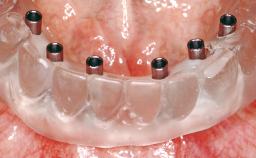

A 63-year-old female patient was referred to the University Medical Center in Groningen, Netherlands, for dental implant treatment. The patient had been edentulous in the upper jaw for 20 years. The remaining teeth in the lower jar had been removed two years before the consultation. The patient was wearing her first maxillary denture and her second mandibular denture; the latter was 1 year old at the time. The conventional upper denture had functioned satisfactorily for many years, but the patient complained about reduced stability and insufficient retention of her lower conventional denture. Her medical history revealed no significant findings. The intraoral examination revealed minor resorption of the maxillary alveolar process and extreme resorption of the mandibular alveolar process.